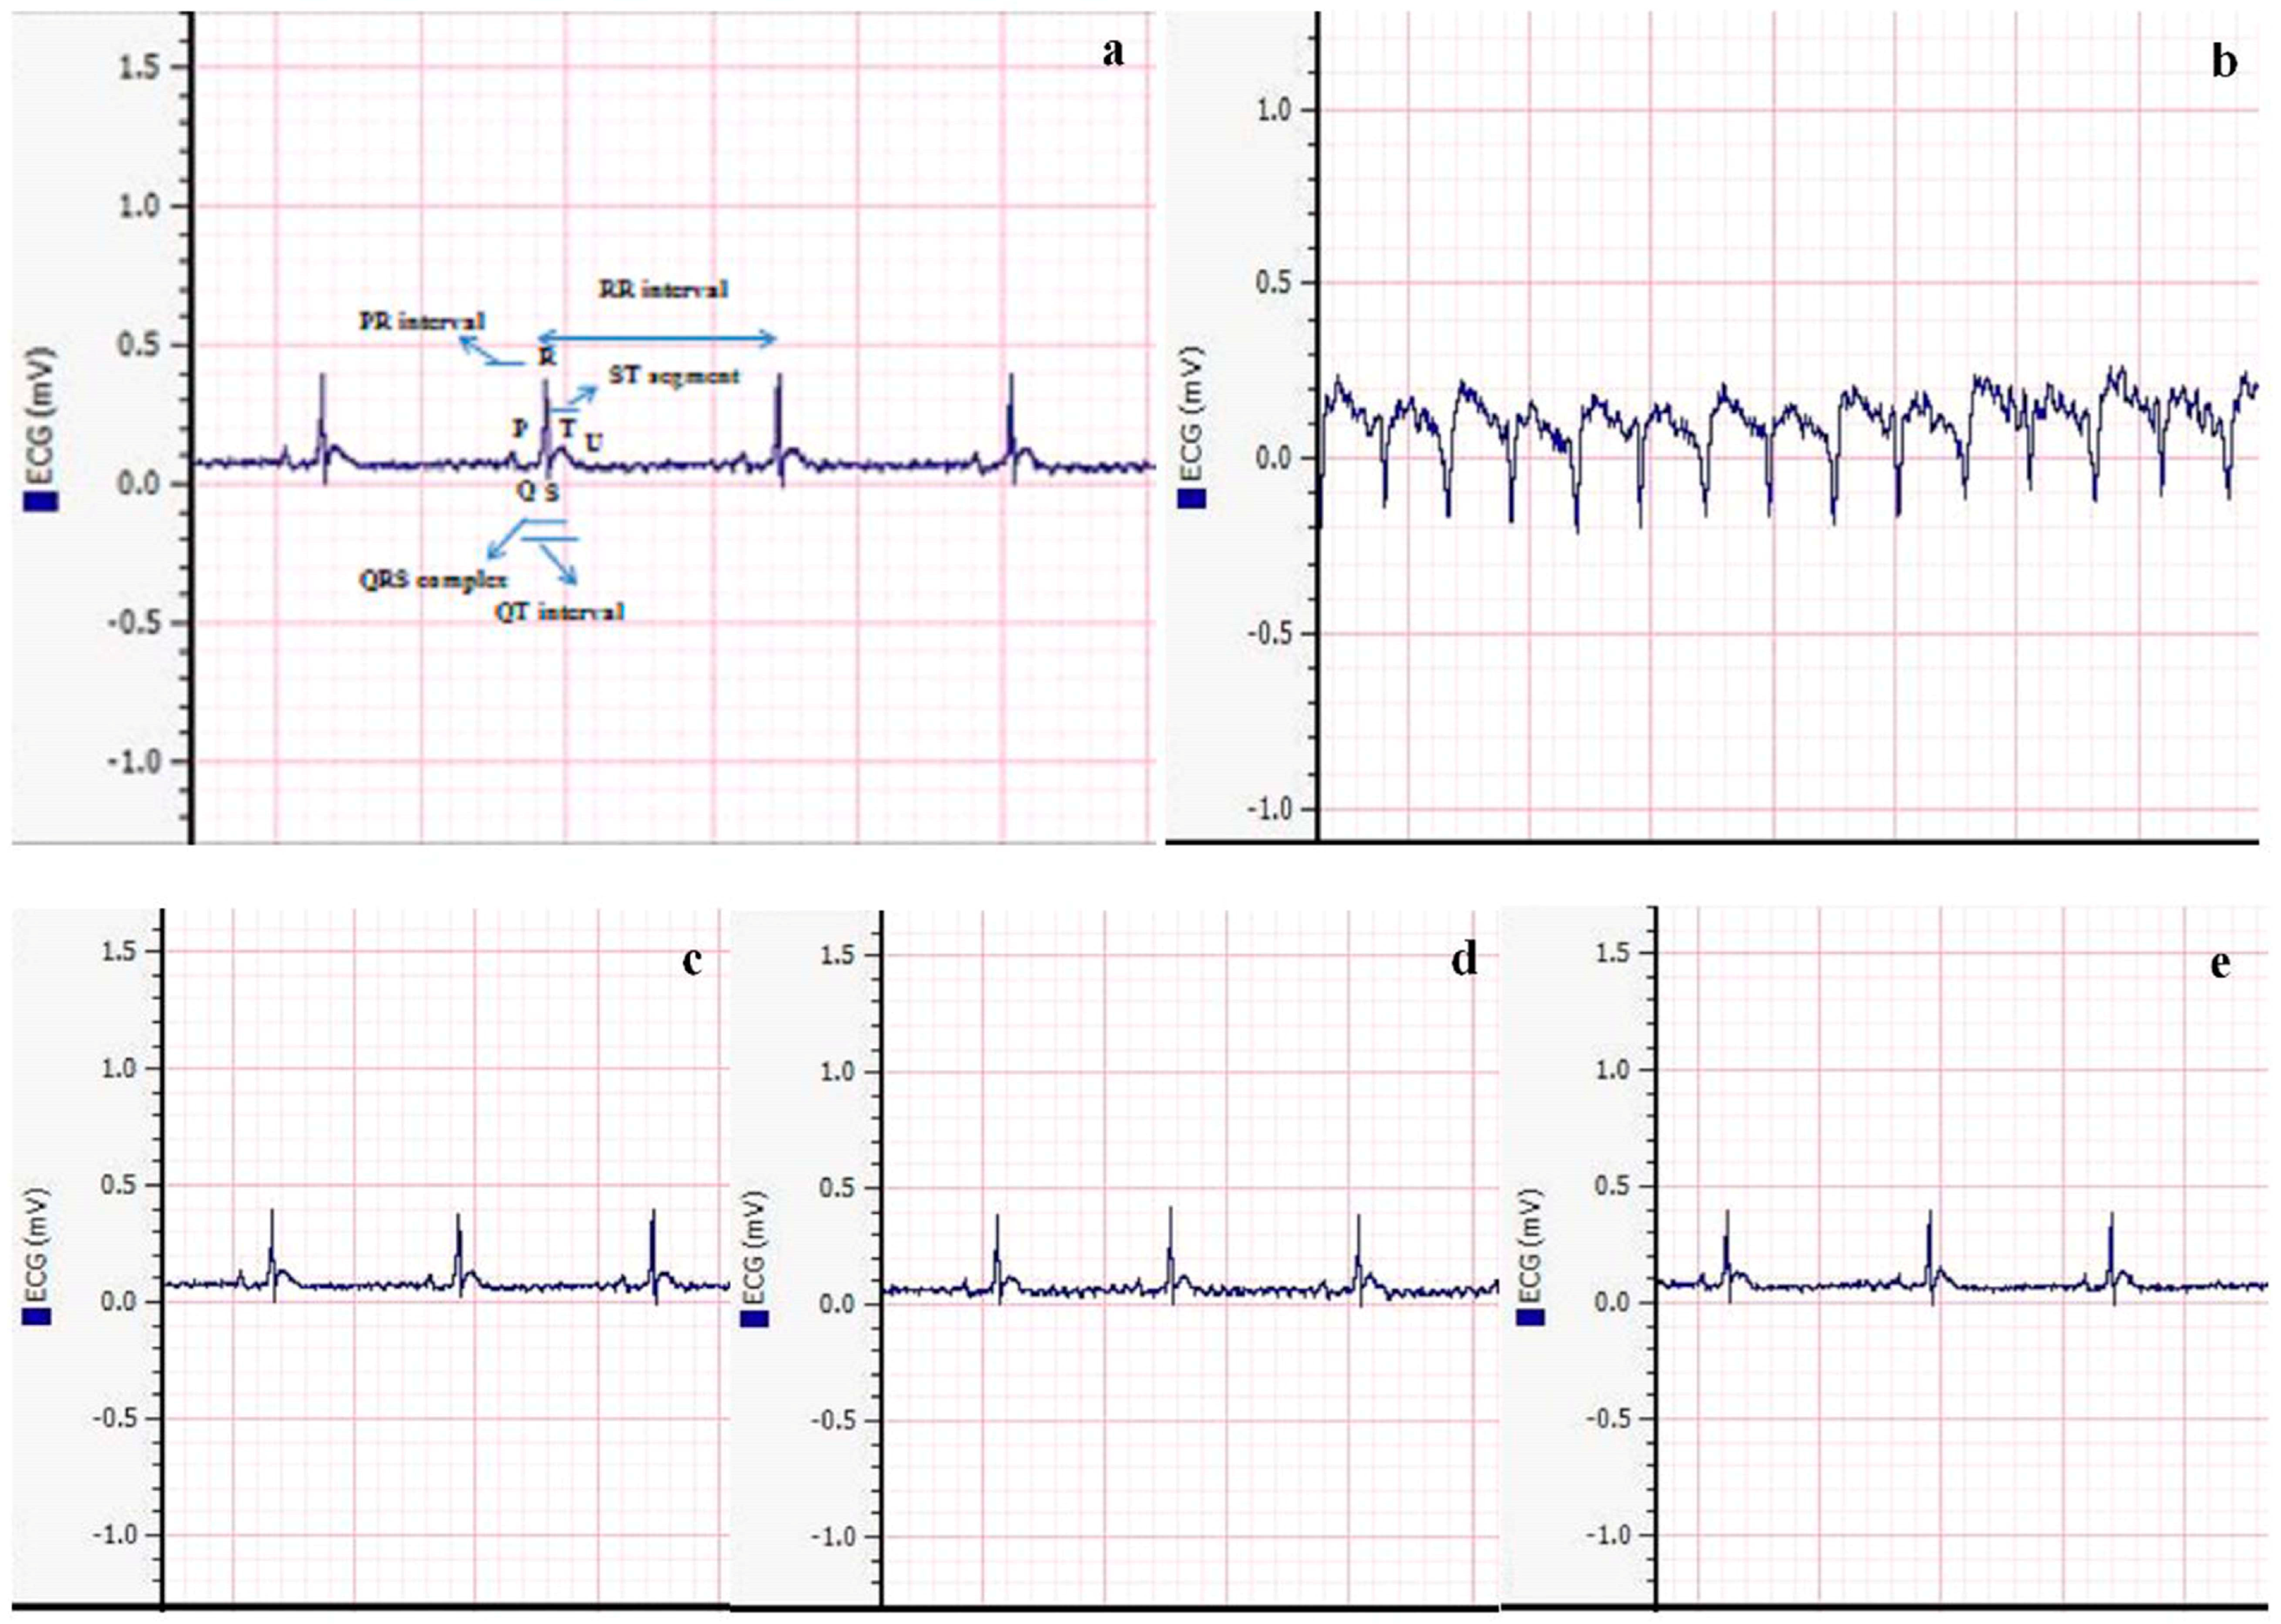

2.9. Analysis of ECG Pattern

Measuring the ECG pattern in neuroinflammation and cardiometabolic disturbance is crucial because it provides valuable information about the electrical activity and rhythm of the heart. Changes in the ECG pattern can indicate cardiac dysfunction or arrhythmias, which are common complications associated with neuroinflammation and cardiometabolic disorders.

After administering anesthesia, the animals from each experimental group were laid flat on the working slab. Electrodes were connected to each arm of the animal, and the standard leads were positioned on the palms of the left and right limbs. The grounded lead was attached to the right hind foot. Subsequently, the Bio Amp cable was plugged into the Bio Amp input, and electric signals were generated and recorded by a device connected to the Power-Lab.

3.6. Analysis of ECG Pattern

In this study, we examined the effects of metformin, vitamin E, and their combination on electrocardiogram (ECG) parameters after inducing neuroinflammation and cardiometabolic disturbance with AlCl3 (Figure 7). In the control group, different intervals, such as QT, PR, and RR intervals, as well as the QRS complex and ST segment, exhibited a normal pattern, indicating a well-functioning cardiovascular system in the absence of AlCl3 exposure. However, the group treated with AlCl3 (50 mg/kg/day) showed an abnormality in the ECG, specifically an inverted QRS complex. The presence of an inverted QRS complex is indicative of impaired ventricular depolarization, which can lead to disturbances in cardiac function and electrical conduction.

Significant improvement in ECG findings was observed after treatment with metformin and vitamin E alone. The ECG parameters in these groups showed amelioration, indicating a positive effect on cardiac function and electrical activity. The normalization of the ECG pattern in these groups suggests that both metformin and vitamin E may have beneficial effects on the cardiac system, potentially mitigating the adverse effects induced by AlCl3. Interestingly, the combination group treated with metformin and vitamin E showed a completely normal ECG pattern. This finding indicates that the combination therapy effectively restored the ECG parameters to their baseline levels, resembling the ECG pattern observed in the control group. This normalization of ECG parameters in the combination group suggests a potential synergistic effect between metformin and vitamin E in protecting the cardiovascular system from the detrimental effects of AlCl3-induced neuroinflammation and cardiometabolic disturbance. The normal ECG pattern in the combination group further supports the idea that the combination therapy may have targeted multiple pathways involved in cardiac dysfunction and inflammation, resulting in the observed improvement in ECG findings.

These findings highlight the potential of the combination therapy as a promising approach to preserving cardiac health and preventing the adverse cardiovascular effects associated with AlCl3 exposure. However, further research is needed to elucidate the specific mechanisms underlying the observed cardioprotective effects and to assess the long-term safety and efficacy of the combination therapy in the context of cardiovascular diseases and related comorbidities.

Metformin’s role in activating brain-derived neurotrophic factor (BDNF) and promoting hippocampal neurogenesis has been linked to the recovery of cognitive dysfunction [47]. Dementia and Alzheimer’s disease (AD) have become significant public health concerns, with millions of individuals affected worldwide. Cognitive decline can have a measurable impact on an individual’s thinking and memory abilities, and vitamin supplementation has been suggested as a strategy to delay the development of cognitive decline in individuals with AD. Among vitamins, vitamin E has shown promise in reducing cognitive decline, acting as a scavenger of free radicals and regulating the synthesis of brain prostaglandin and nucleic acid. Some studies have predicted that vitamin E intake may slow down the progression of AD/dementia in elderly individuals [48,49]. The current study showed a significant improvement in vacuolation after continuous administration of 50 mg/kg/day AlCl3, with recovery observed in the combination therapy group (Figure 6). The normal neuronal structure seen in the metformin + vitamin E group indicates potential benefits in protecting against AlCl3-induced neurotoxicity. The heart’s network of collagen plays a crucial role in cardiac muscle contractility and provides cardiac strength. AlCl3 toxicities have been associated with various cardiac conditions, including myocarditis, DM, fibrosis, ischemic stroke, thrombosis, Alzheimer’s disease, pancreatitis, dementia, and necrosis [19]. Vitamin E has been identified as having anti-inflammatory and antioxidative properties, making it a potential candidate in preventing cardiac fibrosis and protecting the cardiovascular system [19]. Metformin has also shown promise in improving endothelium-dependent microvascular response, decreasing fibrotic tissue development, ameliorating the pro-inflammatory state in atherosclerosis patients, and reducing myocardial ischemia [50]. In the current study, Masson’s trichrome staining of the rat heart revealed fibrotic tissue development around blood vessels after three weeks of continuous AlCl3 administration, while the combination group showed no fibrotic tissue development (Figure 6). Similarly, vitamin E has been reported to prevent or alleviate the adverse effects of organic compounds on pancreatic fibrosis and collagen deposition [51]. In the present study, high fibrotic tissues were observed between acinar cells and around the islets of Langerhans after 45 days of continuous AlCl3 administration. However, no fibrotic tissues were observed in the combination therapy group (Figure 6), indicating the potential protective effect of metformin + vitamin E on pancreatic tissue. Furthermore, long-term exposure to AlCl3 has been associated with cardiac rhythm disturbances, including hypotension, chest discomfort, CNS depression, tachycardia/bradycardia, ventricular and atrial dysrhythmias, shortness of breath, coma, and even death [51,52]. Combination therapy was effective in attenuating AlCl3-induced alterations in the ECG pattern compared to metformin and vitamin E alone (Figure 7). These findings suggest the potential of the combination therapy to protect against AlCl3-induced cardiac rhythm disturbances. Oxidative stress is involved in the pathogenesis of CVDs, such as heart failure, hypertension, and atherosclerosis. The production of ROS is associated with cardiac arrhythmias. ROS and oxidative stress play roles in the development of ventricular fibrillation (VF) and ventricular tachycardia (VT). On the other hand, vitamin E has shown a significant antioxidant role in the treatment of arrhythmias related to QT interval. It has the potential to improve therapeutic outcomes in patients with ischemic heart disease and/or myocardial ischemia–reperfusion syndrome [53]. Research has reported that metformin has cardioprotective effects, including reducing myocardial infarct size, exerting positive effects on cardiac remodeling, preserving myocardium, and enhancing left ventricular functional activity [54,55].